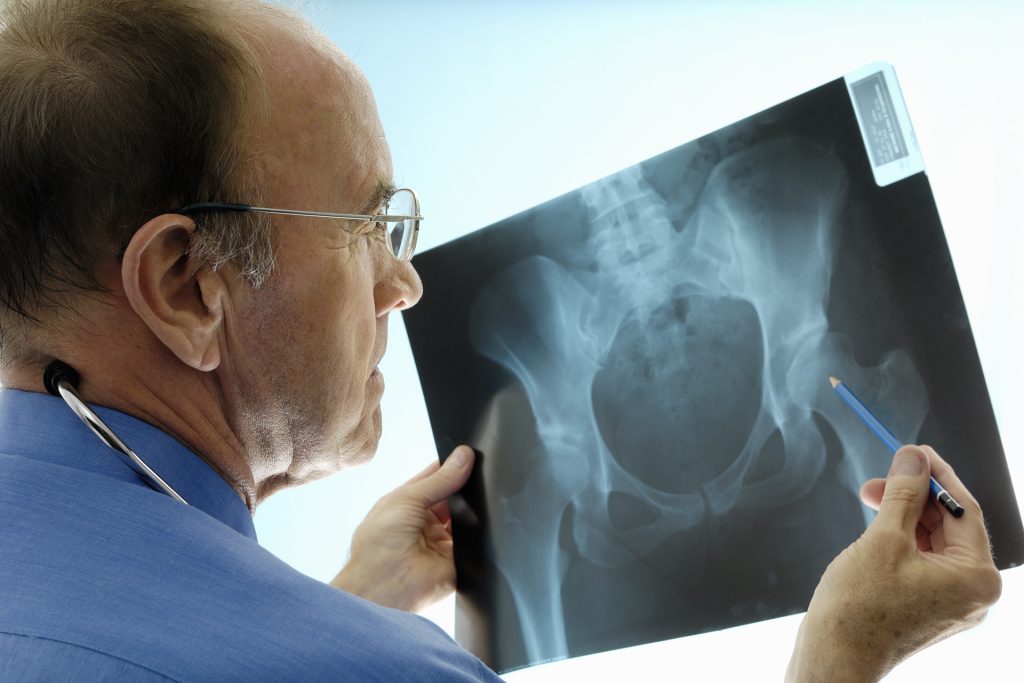

فحص وتشخيص هشاشة العظام

من أجل منع العواقب الوخيمة لهشاشة العظام، من الضروري إجراء فحص منتظم لهشاشة العظام لدى كبار السن.

فحص كثافة العظام

قياس كثافة العظام، المعروف أيضا باسم قياس امتصاص الأشعة السينية الثنائي الطاقة، هو الفحص المرجعي لتقييم كثافة المعادن في العظام. هذا الفحص غير المؤلم وغير الجراحي يجعل من الممكن اكتشاف هشاشة العظام وتقييم خطر الكسور.